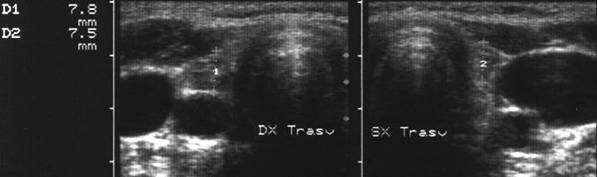

Lob drept, proiectie trasversala. Lob

stang, proiectie trasversala.

Lob drept, proiectie longitudinal. Lob stang, proiectie longitudinala.

Femeie de 41 ani. Tiroida de consistenta dura, foarte

dureroasa la palpare, cu suprafata neregulata.

Ecografia: moderata crestere a volumului; marginile lobilor rau definite; structura

intens ne mogena cu alternanta de arii hipoecogene, de edem si altele intens ecogene,

cu aspect pseudonodular.

Examene de laborator: moderat hipertiroidism; indici de fibroza foarte ridicati.